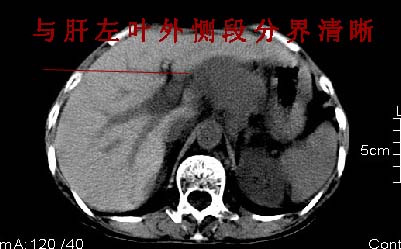

ct:肝胃之间、胰头后、腹主a周围,融合而成团块状影,包绕血管,胰腺前移后缘分界欠清,与肝胃分界清,肿块未见明显强化,肝右叶后段小囊肿。

肝胃之间、胰头后、腹主a周围,融合而成团块状影,包绕血管,胰腺前移后缘分界欠清,与肝胃分界清,肿块未见明显强化,考虑淋巴瘤可能性大

肝胃之间、肝十二指肠韧带,胰头后、腹主a周围,融合而成团块状影,包绕血管[腹腔干、肠系膜上动脉,腹主动脉],胰腺前移后缘分界欠清,与肝胃分界清,肿块未见明显强化,肝右叶后段小囊肿。

主动脉-胰腺间隙可见巨大分叶状软组织肿块影,包绕腹主动脉、腹腔干及其分支、腔静脉等大血管,增强呈无明显强化,临近脏器明显受压移位,增强示有分界。肝右叶可见局限性低密影,边缘清楚。